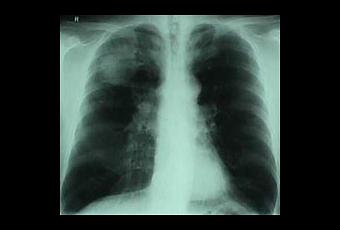

La proteína que se tuvo que corregir mediante modificación genética fue la alfa-1-antitripsina, activa en el hígado y que protege de inflamaciones excesivas. Si falla el gen, la proteína no sale correctamente del hígado y acaba causando cirrosis hepática y enfisema pulmonar, enfermedad que afecta a una de cada 2000 personas del norte de Europa.

Para la inserción del gen correcto se utilizó un transportador de ADN específico denominado piggyBac el cual, tras finalizar su trabajo, era eliminado completamente dejando una célula completamente sana. Las células curadas, convertidas en hepáticas, producían alfa-1-antitripsina cuándo y cómo debían.